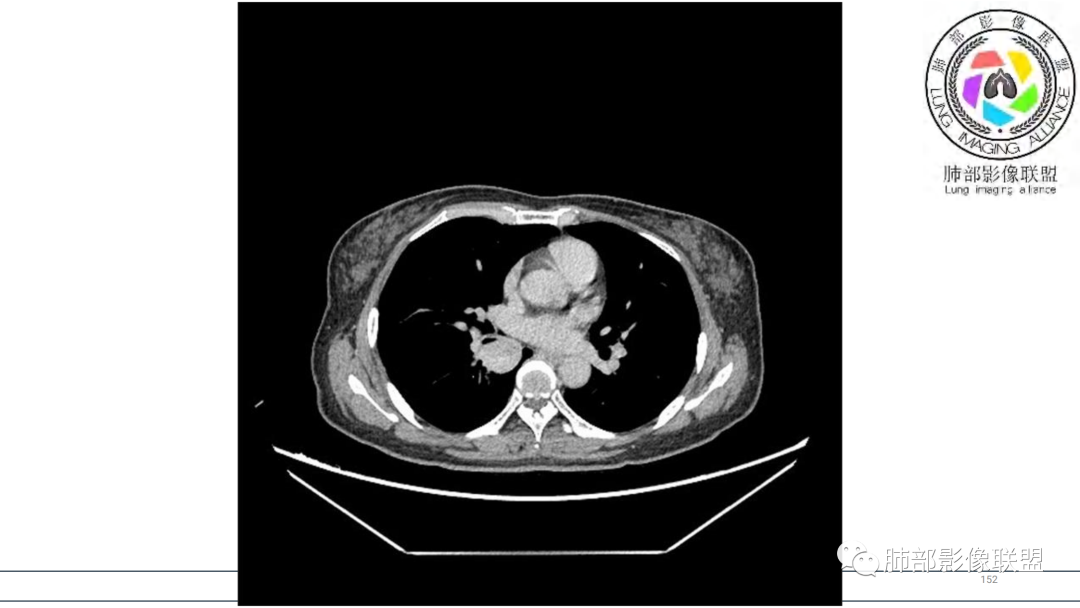

2.右肺下叶及中间段支气管后方类圆形块影,边界较清楚,未见分叶及毛刺,病灶部分突入支气管腔内(冰山一角),局部管腔狭窄,相应肺叶未见片影或体积变化。

3.块影密度均匀,未见液化坏死及钙化,渐进性强化,强化显著。

中青年女性,支气管管腔内外肿块(“冰山征”),边界较清楚,强化显著,未见阻塞性肺不张,尽管未出现“类癌综合征”临床表现,仍然符合典型类癌影像学表现。

类癌临床表现无特异性,影像学检查仍然是肺类癌的主要诊断依据。其特征性表现是孤立的、边界清楚的肿物,密度可均匀或不均匀,边缘多清楚锐利,部分病例可见浅分叶及毛刺。类癌侵及的支气管局部增厚,与正常的管壁分界清楚,局部呈乳头状突起,表面光滑。肺门旁肿块往往边缘光整、轮廓清楚、密度均匀,增强扫描大多呈均匀明显强化,可有持续强化或延迟强化。中央型肺类癌可引起支气管壁局限性增厚,形成轮廓光滑的管壁结节,并与腔外大病灶形成“冰山征”。少数病例可沿支气管腔内长轴生长,呈指套样改变,类似肺鳞癌,但较肺鳞癌血供丰富。